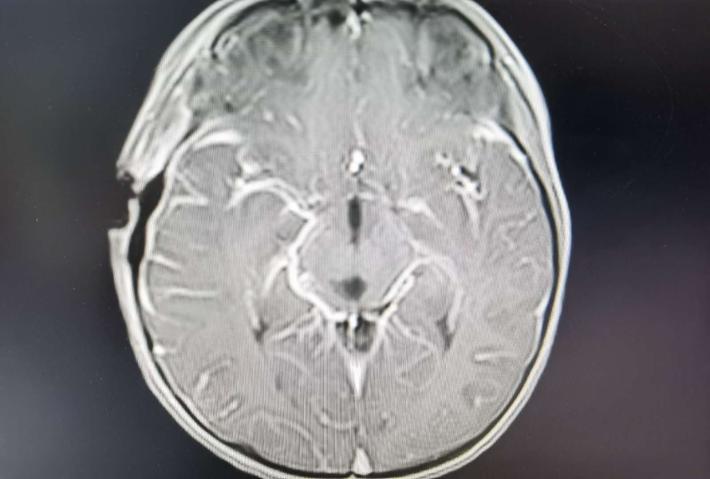

术后轴位,肿瘤消失,导水管通畅

术后轴位,肿瘤消失